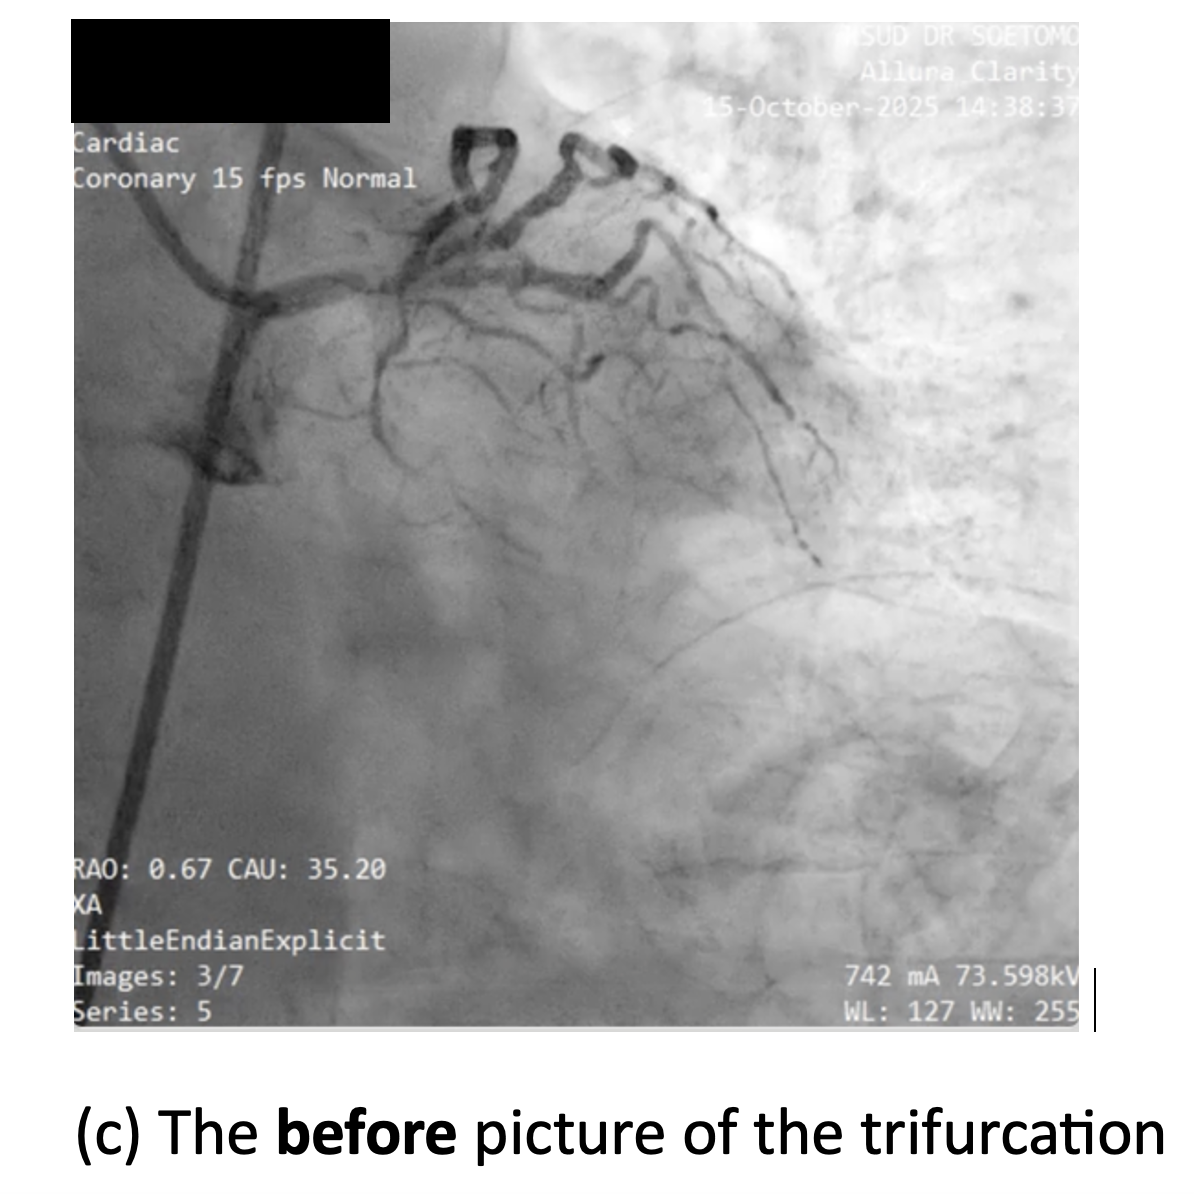

Relevant Catheterization Findings

Diagnostic coronary angiography revealed a right-dominant coronary circulation with 80% distal left main stenosis involving the LAD, LCx, and Ramus Intermedius (Medina 1-1-1-1 true trifurcation). The LAD showed 90% ostial-proximal stenosis, the LCx 90% ostial stenosis, and the RI 90% proximal stenosis. There was a non-significant 40% stenosis at the mid-distal RCA with extensive collateral flow to the distal LCx, LAD, and septal branches via the conus branch, RPLB, and RPDA.

Using right femoral access with 7F long sheath, elective PCI was performed employing a Triple-kissing-balloon (Trissing) technique used for trifurcation lesions. The technique consisted of: (1) Engaging left main with BL 3.0 7F guiding catheter (GC) and guiding wire (GW) to three branches (GW BMW guidewire to LAD, GW Runthrough Hypercoat NS to LCx, and GW Whisper to Ramus Intermedius); (2) Stenting the main vessel with DES Xience Xpedition everolimus-eluting stents (Abbott Vascular, USA) 3.5 ¡¿ 23 mm to distal LM - proximal LAD; (3) Proximal optimization technique (POT) for MB stent; (4) Rewiring and assessment of side branches, followed by T-stenting and small protrusion (TAP) technique at the first side branch with DES Xience Xpedition everolimus-eluting stent 3.0 ¡¿ 18 mm to osteal-proximal LCx; (5) Evaluation of the second side branch, Ramus Intermedius, and followed by second TAP using DES Xience Xpedition everolimus-eluting stent 2.5 ¡¿ 15 mm at ostial-proximal of Ramus Intermedius; complemented by kissing balloon inflation (KBI); (6) Final POT; (7) Third trissing balloon inflation across all three branches to optimize stent apposition. Total heparin administered was 8500 units. Final angiography demonstrated TIMI 3 flow in all vessels with complete revascularization. Total contrast volume 210 mL using Iohexol, with total fluoroscopy time is 45.6 minutes, dose-area product 114 Gy¡¤cm©÷. No periprocedural complications occurred.